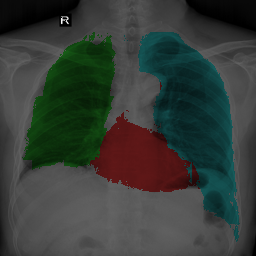

To bridge the methodological gaps when only small-scale partially labeled data is available, we propose a simple yet efficient framework Vicinal Labels Under Uncertainty (VLUU) by exploring the statistical similarity of human structures (e.g. shape, size, location) among different patients. See Fig. 1 for an illustration of such a similarity. The proposed framework is motivated by vicinal risk minimization (VRM) [11], where the fully labeled vicinal examples are generated by linearly combining randomly sampled partial labels with a weight randomly sampled from a Dirichlet distribution. These vicinal examples allow us to transform the partially supervised problem into a fully supervised one. That is to say, we can utilize any existing supervised segmentation networks and loss functions to solve partially supervised problems. The generated vicinal labels contain uncertainty regions where classes of interest could potentially overlap. We utilize these uncertainties in the training process to improve the robustness of DL models.

In standard adversarial training, the segmentation network and the discriminator play a zero-sum game. The discriminator is trained to discriminate the prediction masks produced by the segmentation network from the ground truth masks. Meanwhile, the segmentation network is trained to confuse the discriminator by producing realistic prediction masks. Adversarial training benefits from the human structure similarity as it makes the unknown true label distributions easier to be caught by the discriminator than for general objects [38]. In other words, there is smaller instance-wise variation in the size, shape, and location of human organs (or structures), as shown in Fig. 1, than for general objects.